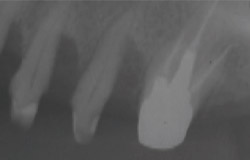

歯周病が進行して、歯の根元まで炎症が広がることがあります。右の写真をご覧ください。赤丸で囲んだ分が黒くなっています。ここは、歯肉が衰え、歯と歯肉の間にできたすき間です。ここに付着した歯石を取り除くことはできません。放置すると歯周病がさらに進行して、やがて抜歯となってしまうでしょう。

そこで、外科的手術で歯の根を露出させて歯石を取り除きます。さらに歯の根の間に歯間ブラシが入るように穴をあけ、お手入れしやすくします。この術式を「トンネリング」といいます。